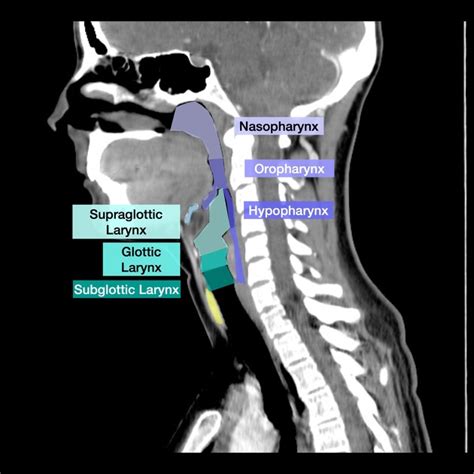

Alright, first things first, let’s get our heads around what Oropharyngeal SCC actually is. The oropharynx is a super important part of our throat, located right behind the oral cavity. It includes structures like the base of the tongue, the soft palate, the tonsils, and the pharyngeal walls. Pretty vital stuff for breathing, eating, and speaking, right? When we talk about Squamous Cell Carcinoma , we’re referring to cancer that starts in the squamous cells, which are the flat, thin cells that make up the lining of these parts of the throat. Oropharyngeal SCC is a significant subtype of head and neck cancers, and its incidence has been on the rise, particularly in certain populations. Understanding the anatomy of the oropharynx is the absolute first step in appreciating how SCC can develop and spread. Think of it as the gateway to your digestive and respiratory systems, and unfortunately, it can become a site for aggressive cancer development. The term ‘SCC’ just refers to the specific cell type where the cancer originates, and in this region, it’s the most common type. Now, the etiology of Oropharyngeal SCC is also something we need to touch upon, as it significantly impacts the patient population and often influences diagnostic approaches. Traditionally, heavy tobacco and alcohol use have been major risk factors. However, in recent decades, there’s been a dramatic increase in Oropharyngeal SCC linked to the Human Papillomavirus (HPV), specifically HPV types 16 and 18. This HPV-associated oropharyngeal cancer often affects younger, non-smoking individuals and tends to have a better prognosis compared to HPV-negative tumors. This distinction is critical for treatment planning and patient counseling. So, when you encounter a case of oropharyngeal malignancy, always consider the HPV status, as it changes the game entirely. The disease can present as a primary tumor within the oropharyngeal structures, or it can be part of a larger metastatic process. The implications of an oropharyngeal SCC diagnosis are profound, affecting not only the patient’s physical health but also their quality of life, due to the critical functions of this anatomical region. Early detection through imaging is paramount to improving outcomes, which is where resources like Radiopaedia become indispensable for healthcare professionals aiming to accurately identify and characterize these lesions. The complexity of the oropharynx, with its numerous folds, fossae, and lymph node stations, makes imaging interpretation a nuanced art requiring a thorough understanding of both normal anatomy and the diverse ways malignancy can manifest. We’ll be exploring the subtle signs and definitive indicators that radiologists look for when assessing scans for this type of cancer.

Now, let’s get down to the nitty-gritty: what are the actual key imaging findings we look for when assessing Oropharyngeal SCC , especially when referencing resources like Radiopaedia? It’s all about recognizing the patterns and deviations from normal anatomy. The primary tumor itself can manifest in several ways on imaging. It might appear as a focal thickening of the oropharyngeal mucosa , which can be subtle and easily missed if you’re not paying close attention. Sometimes, it presents as an irregular mass lesion , often with associated enhancement after contrast administration, indicating increased vascularity – a hallmark of malignancy. The location is also crucial. Oropharyngeal SCC commonly arises from the tonsillar fossa , the base of the tongue , or the posterior pharyngeal wall . On CT, you might see a soft-tissue mass that enhances avidly. On MRI, T2-weighted images can show a T2-hypointense (darker) mass, while post-contrast T1-weighted images reveal heterogeneous enhancement. Invasion into surrounding structures is a critical staging factor. Look for erosion of the medial pterygoid muscles , parapharyngeal space involvement , or extension towards the larynx or hypopharynx . On CT, this might manifest as ill-defined margins or frank destruction of adjacent soft tissues. MRI excels here, clearly showing obliteration of fat planes and invasion into muscles. Now, let’s talk about the lymph nodes, guys. This is HUGE. Cervical lymphadenopathy is a very common finding in Oropharyngeal SCC . We’re not just looking for enlarged nodes; we’re looking for suspicious features. In a node, suspicious characteristics include: enlargement (typically >10mm short axis diameter on CT, though this can vary), rounded morphology (instead of the normal oval shape), loss of the fatty hilum , and rim enhancement after contrast. Radiopaedia has tons of examples showing these features. Necrosis within a lymph node, appearing as a central dark area on MRI or low-attenuation area on CT, is also highly suspicious for metastatic involvement. Don’t forget about the level of the lymph node in the neck. Metastases from the oropharynx typically spread first to the upper deep jugular chain nodes (Level II) and the mid-jugular nodes (Level III) . Identifying involved nodes in these specific levels is critical for accurate staging and treatment planning. Sometimes, you might see direct extranodal extension (ENE) , where the tumor has spread beyond the lymph node capsule into surrounding tissues. This is a significant adverse prognostic factor and can be challenging to detect on imaging, but subtle stranding of soft tissues around a lymph node or direct contiguity with other structures can be clues. Radiopaedia’s image library is an invaluable tool for learning to recognize these subtle signs of ENE, comparing different modalities and viewing cases with confirmed pathological findings. Recognizing these specific imaging characteristics – the appearance of the primary tumor, its local invasion patterns, and the morphological features of cervical lymph nodes – is the cornerstone of diagnosing and staging Oropharyngeal SCC accurately. It’s about piecing together these clues to build a comprehensive picture of the disease for the patient’s treatment team.